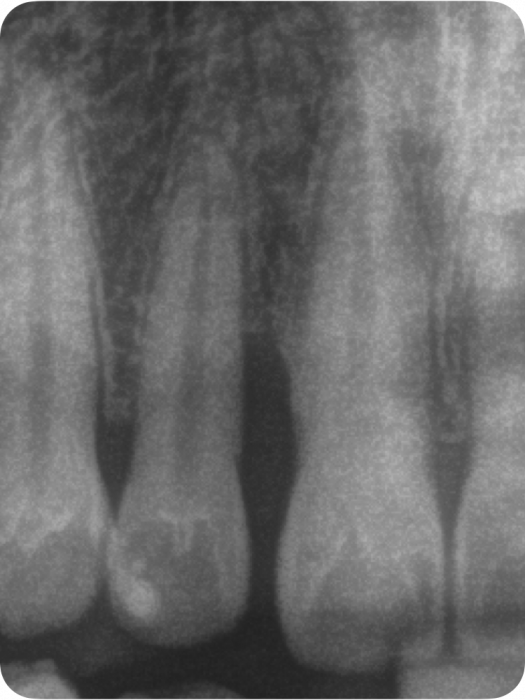

Der Grad enthält Informationen zur Progressionsrate der Erkrankung und dem Vorliegen von patientenspezifischen Risikofaktoren (Nikotinkonsum und Diabetes/HbA1c). Die Progressionsrate kann direkt anhand von Vorbefunden abgeschätzt werden oder indirekt durch den sogenannten Knochenabbauindex (KA %/Alter). Dabei wird der Zahn auf dem Röntgenbild berücksichtigt, der den stärksten marginalen Knochenabbau hat. Das Vorliegen von Risikofaktoren kann zu einem Upgrade führen. Fehlen diese Risikofaktoren, führt das aber nicht zu einem Downgrade.